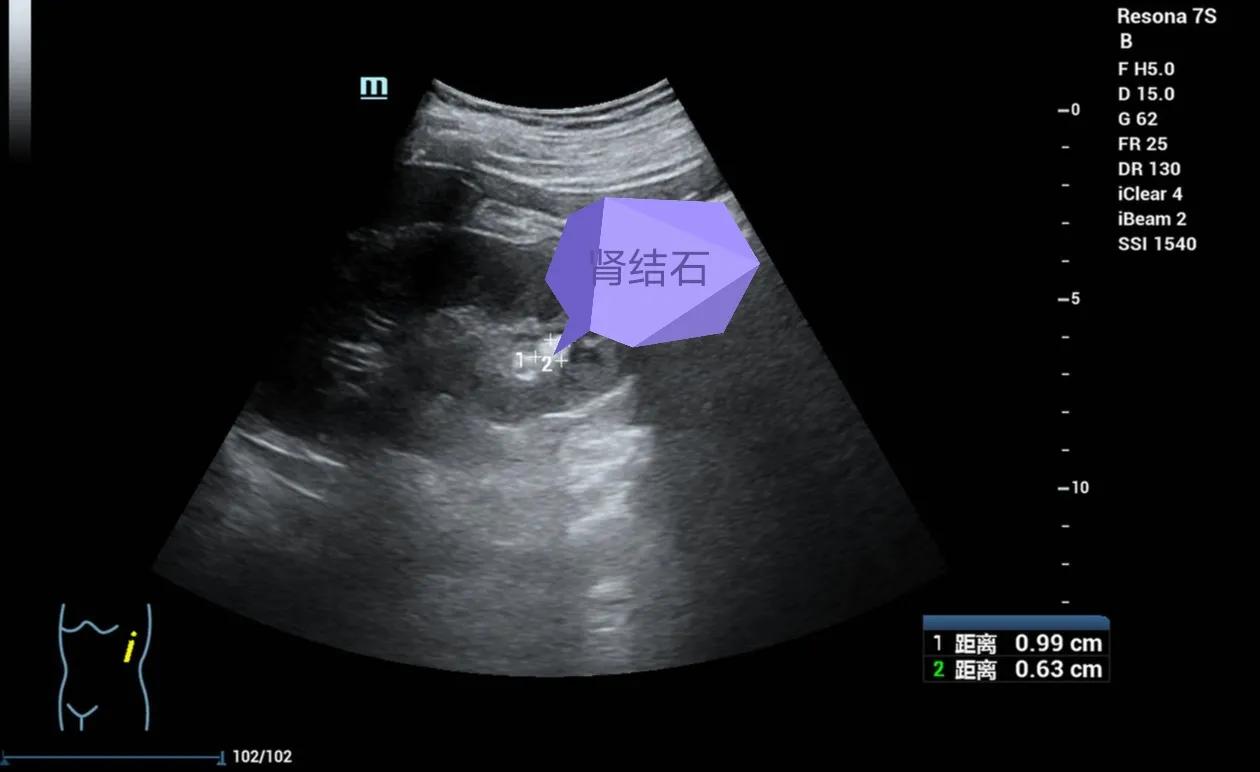

图中箭头所示的亮亮的强回声斑便是结石,大小9.9*6.3mm